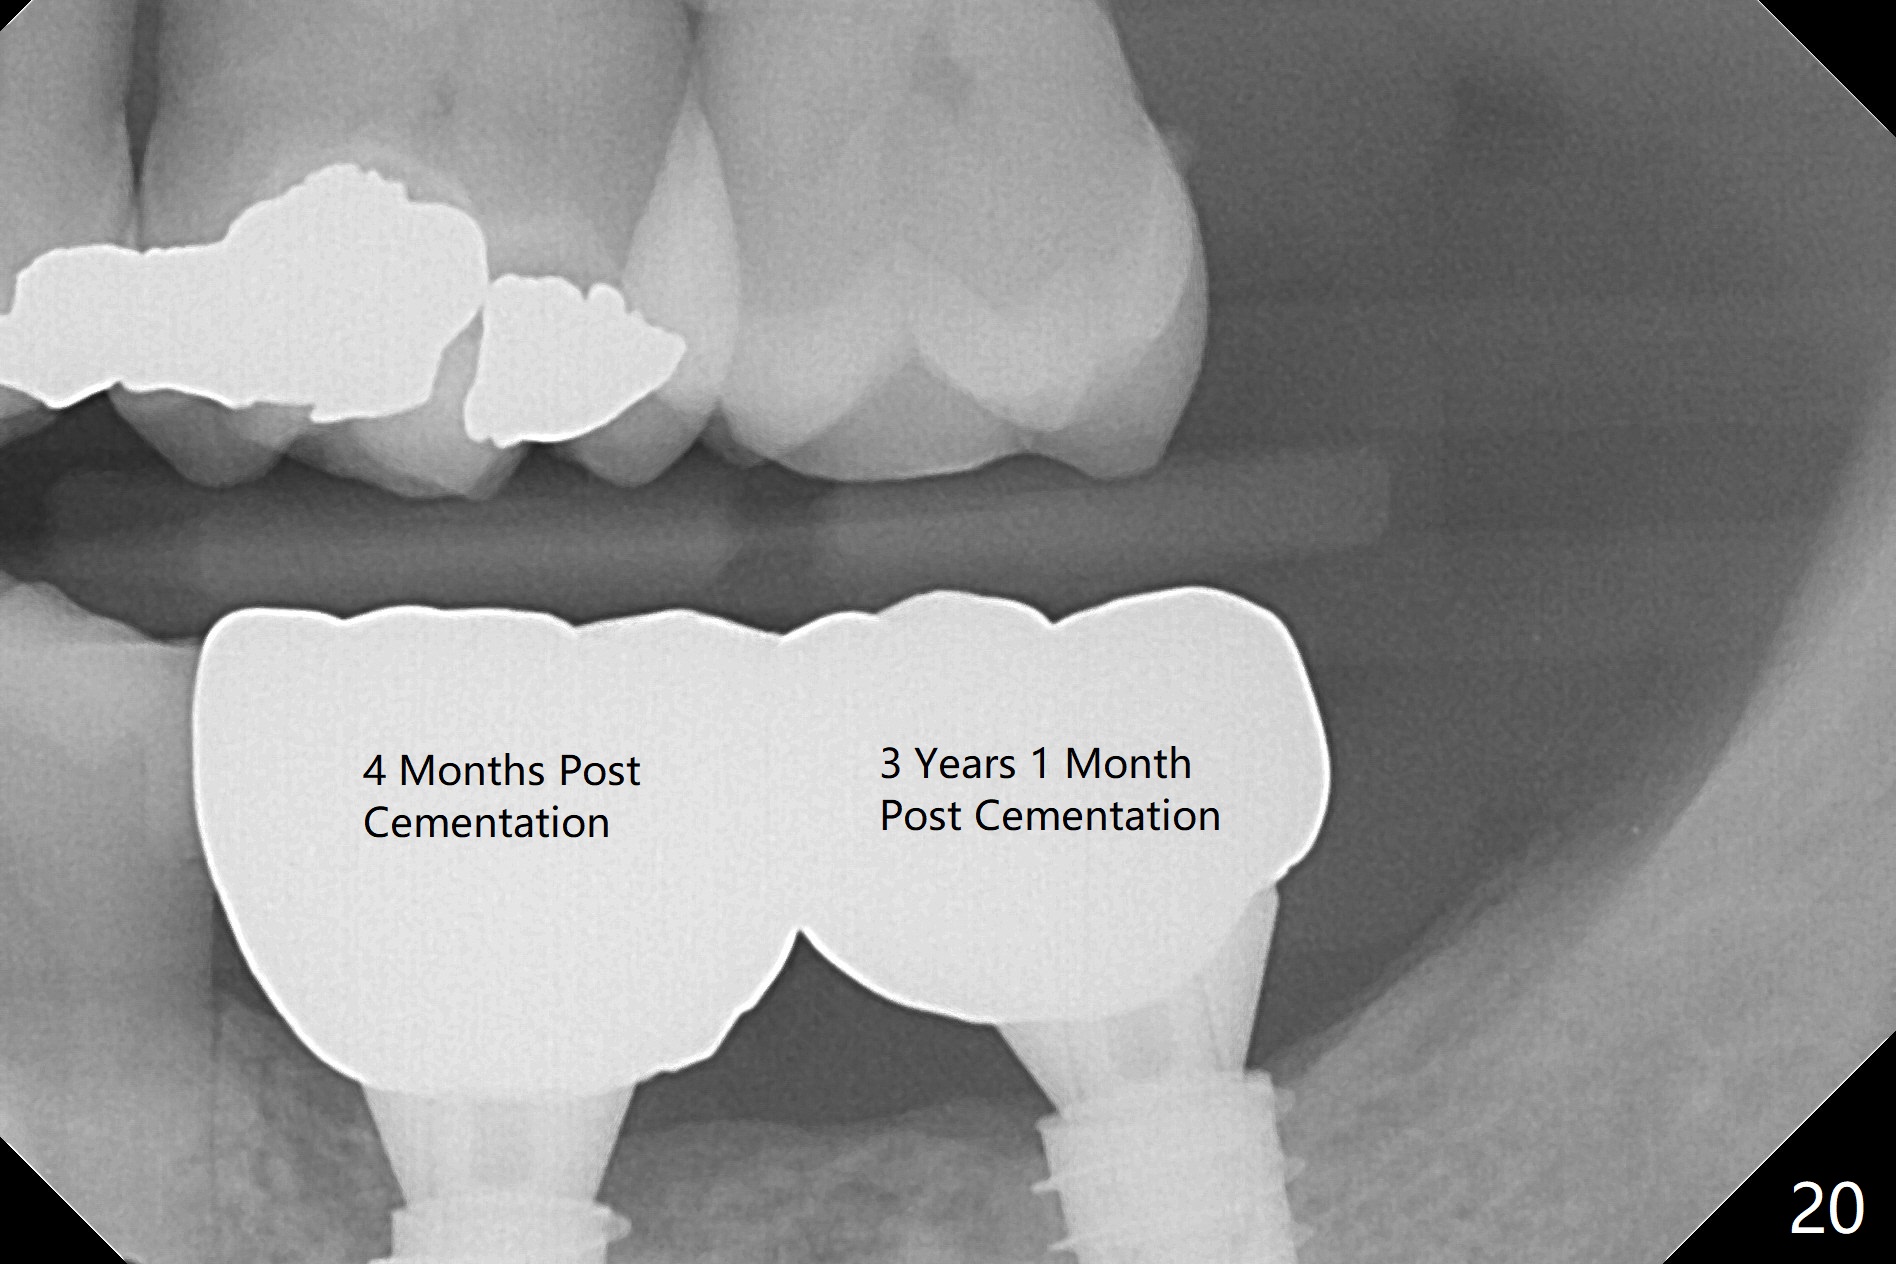

Venopuncture is conducted (Fig.1) for PRF and sticky bone (cortical chip and .5 cc ß-TCP). After use of proximators at #19, cowhorn forceps are applied, resulting in metal crown dislodgement. Since there is distal bone loss, distal socket sheath is contemplated. The tooth is sectioned. When an elevator is inserted between the roots, the distal root is loosened first. The 2 roots are removed, revealing a rounded end septum (Fig.2 S) and a larger distal socket. To avoid osteotomy deviation over the septum, a 12 mm bone trimmer is used, followed by point drill (Fig.3 *). But the lower half of the implant is deviated mesial (Fig.4) with decreased torque (~ 10 Ncm). To overcome this misfortune, the roots should not be removed until osteotomy is finished. Dual zones of bone graft is conducted. Sticky bone is placed until the plateau of the implant with a healing screw in place (Fig.4 * (bone zone)). After placement of a pair abutment, the same bone graft is packed until the margin of the abutment (Fig.5 * (soft tissue zone)). An immediate provisional is fabricated to close the socket with a piece of PRF as well. Fig.6-11 explains why the lower half of the implant deviates to the mesial socket, while Fig.12-16 illustrates how to prevent the deviation. After extraction of #19 (Fig.6,7), the crest of the septum is flattened (Fig.8 arrowhead) to prevent the initial deviation (Fig.9 red line). When a drill reaches a space (a socket, mesial in this case), the drill is deflected to the least resistant area (Fig.10 a bent red line), leading to the implant deviation apically (Fig.11 green). To prevent the apical deviation, therefore, the roots of the affected tooth is temporarily not removed (Fig.12). The osteotomy should not deviates with surgical guide because of similar density between the tooth and the bone (Fig.13). When the osteotomy is finished (Fig.14), the roots are extracted (Fig.15). The implant to be placed should not have deviation (Fig.16 green). The papillae are maintained by the immediate provisional 11 days postop (Fig.17). The incompletely seated abutment at #18 (Fig.5 <) is reseated completely 6 months postop (Fig.18). Crestal bone forms distal to #19 implant. There is no bone loss 4 months and 3 years 1 month post cementation at #19 and 18, respectively (Fig.19,20).